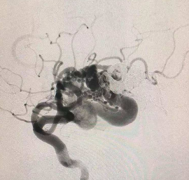

脑动静脉畸形 (AVMs)是常见的血管疾病,其较常见的表现为出血,约半数患者出现出血。AVM的破裂率在2% - 4%之间。一些神经外科医生认为,较小的动静脉平...

颅内动静脉畸形的诊断和评估,显微外科切除仍然是仔细选择的动静脉畸形的优选治疗方法,因为它可以立即明确地排除AVM。为此,已有许多AVM分类体系被...

动静脉畸形( arteriovenous malformation,AVM)是一种具有挑战性的脑血管病变。脑动静脉畸形栓塞术怎么做?...

脑动静脉畸形病理学和临床特征。 (arteriovenousmalformation)脑动静脉畸形AVM)是颅内较常见的血管畸形之一,以动脉和静脉经血管畸形的血管团相连为特征,二...